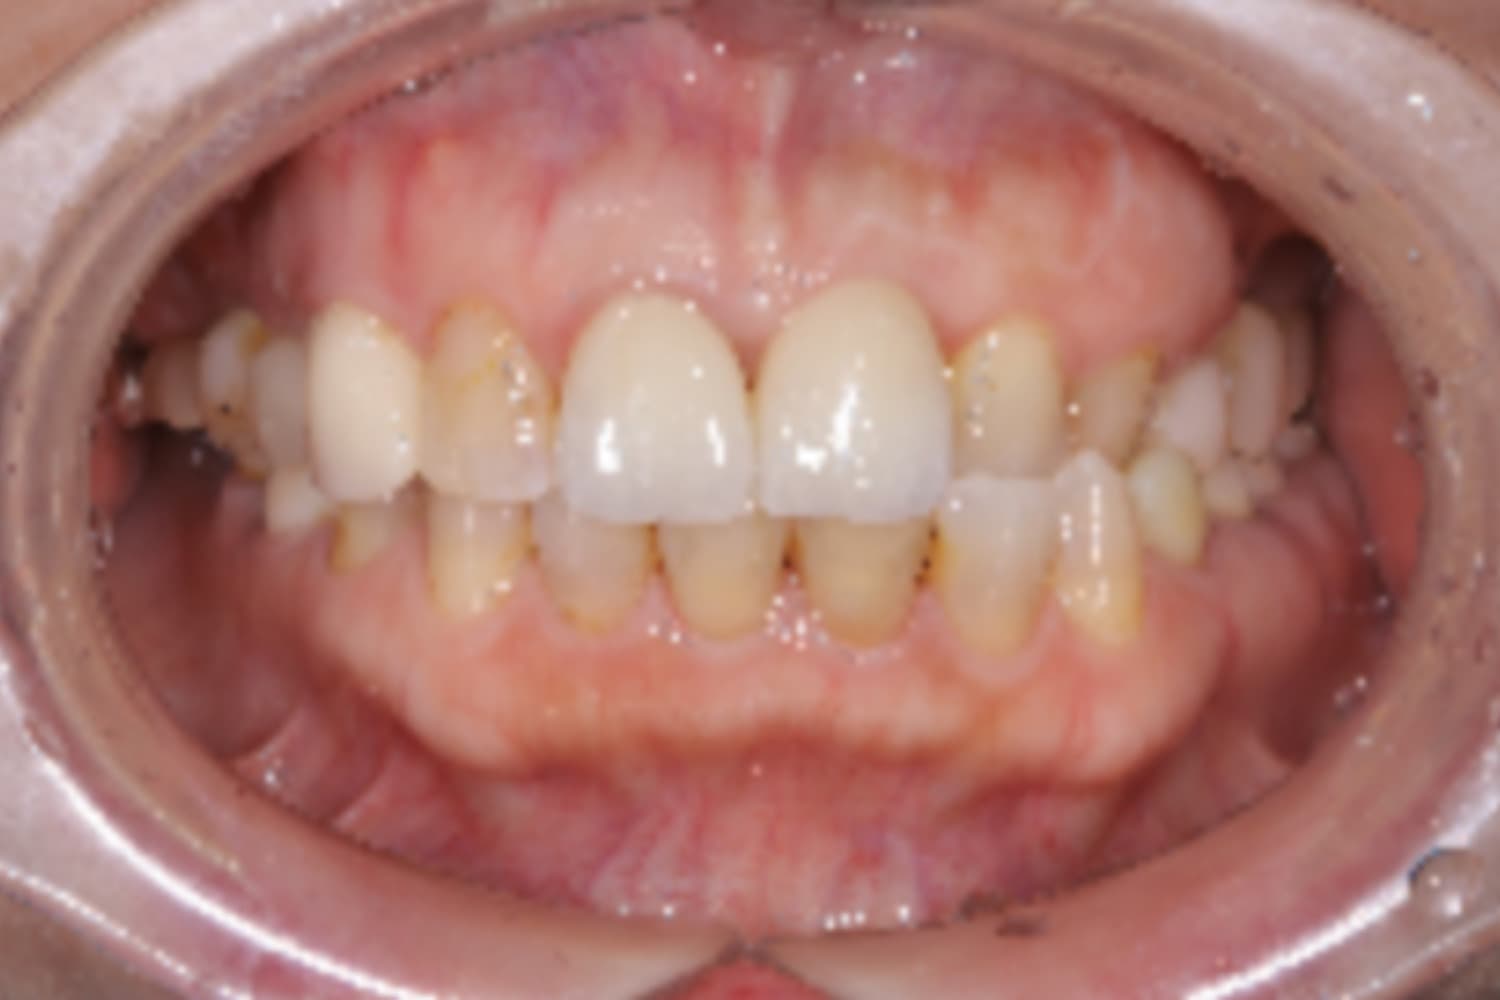

前歯のインプラント治療

Before

After

前歯4本を抜歯し、その後2本のインプラントと骨造成を行いました。上部構造は4本分です。

主訴

前歯が気になる

治療期間

12カ月

治療回数

12回

費用

1,276,000円

副作用・リスク

・重度歯周病により、感染リスクが高い ・インプラントとの結合不良が起きる可能性がある ・手術前に歯周病の十分なコントロールが必要 ・治療後も1〜2カ月ごとの定期メインテナンスが必須